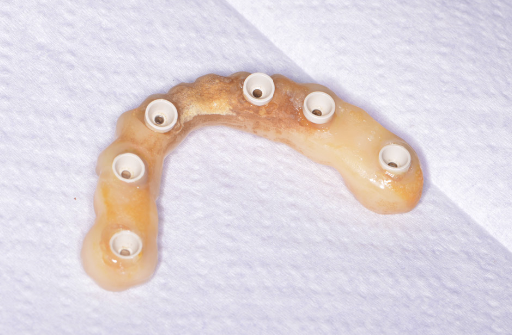

Pe baza scanărilor imagistice 3D (CBCT) se vor efectua măsurători ale înălțimii și lățimii osului mandibular, astfel încât medicul implantolog să poată decide dacă se pot insera implanturi direct sau este nevoie de adăugare de os în prealabil. Se realizează un ghid chirurgical care ajută la poziționarea precisă a implanturilor în os (Fig.3.6.4. dr. Ondine Lucaciu), iar în 24 de ore după această intervenție pacientul primește o punte provizorie fixă pe care o va purta un interval de 3-6 luni, perioadă necesară osteointegrării implanturilor, respectiv vindecării (Fig. 3.6.5). Această lucrare provizorie va fi înșurubată în 6 puncte, în cele 6 implanturi inserate în mandibulă (Fig. 3.6.6).

După acest interval lucrarea provizorie se îndepărtează, în fiecare implant se montează câte un dispozitiv necesar realizării amprentelor (Fig. 3.6.7) care vor servi tehnicianului dentar pentru realizarea punții definitive (Fig. 3.6.8 și Fig. 3.6.9). Realizarea acesteia se face în câteva zile, interval în care pacientul va continua să poarte lucrarea provizorie realizată inițial.